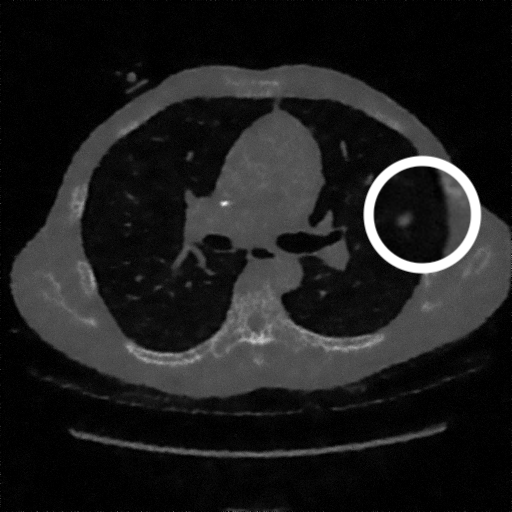

3.1.3 Example 2: data driven reconstruction methods in lung CT screening

There is sufficient evidence that screening for certain tumours using CT images may improve prognosis of cancer survivability (citep \@BBN(Boiselle, 2013)). As mentioned above, in order to gain better image quality with less X-ray dose, many enhanced regularization techniques with integrated machine learning steps have been suggested for CT reconstruction, and in a full reference setting they are commonly evaluated by applying PSNR and SSIM, see e.g. (citep \@BBN(Adler and Öktem, 2018; Hendriksen, Pelt, and Batenburg, 2020; Unal, Ertas, and Yildirim, 2021)). As CT images are generally taken to perform a clinical task, they are not the final step of a medical process but often the initial one. Therefore the definition of what makes a good image heavily depends on the task in hand, and for prognosis related cancer the identification of tumours is of upmost importance.

In on-going research on photon counting detector types and screening procedures for lung cancer (EPSCR grant: EP/W004445/1) an experiment was conducted testing enhanced reconstruction algorithms. Simulations using less than 10% of a clinical X-ray dose were performed to investigate if data-driven methods could sufficiently enhance the images to clearly see the tumours in the lungs while providing very low amount of dosage to the patients. The corresponding data was a CT-dose simulation, using images from the open LIDC-IDRI dataset (citep \@BBN(Armato et al., 2011)) as references, as well as simulated and reconstructed images with in-house software. Figure 3 shows the results of the experiment. We show the reference image used as basis for the simulation, together with five different reconstruction algorithms. The first is an iterative solver, a gradient descend algorithm with TV minimization (citep \@BBN(Sidky et al., 2012)) and (c)-(f) correspond to machine learning methods: FBPConvnet is a denoising algorithm that cleans the bad image (citep \@BBN(Jin et al., 2017)), LPD is an iterative unrolled method that combines traditional solvers with machine learning (citep \@BBN(Adler and Öktem, 2018)), Noise2Inverse is a self-supervised learning method (i.e. does not require ground truth data) (citep \@BBN(Hendriksen et al., 2020)) and ItNet is another iterative unrolled method, the best performing winner of the AAPM DL-Sparse-View CT challenge (citep \@BBN(Genzel, Macdonald, and März, 2021)). ItNet is also judged here as the best result according to PSNR, SSIM and LPIPS.

Refer to caption

(a) Reference

(b) (27.6, 0.70, 0.37)

(c) (31.9, 0.73, 0.29)

(d) (32.5, 0.84, 0.19)

(e) (32.5,0.77, 0.20)

(f) (33.0, 0.89, 0.12)

Figure 3: Reference image (a) and outputs of different reconstruction methods (b)-(f) applied to dose simulated data. PSNR/SSIM/LPIPS are unable to identify the best reconstruction (c), where also the tumour is visualized well.

FR-IQA mismatches

This experiment was performed to evaluate the quality of different kinds of CT reconstruction, and especially the lung tumour detection capabilities thereof. The best result according to the chosen IQA measures is given by ItNet in Figure 3(f), which performs visually poorly. Not only the tumour (zoomed in white circle) is significantly less visible in the reconstruction, but ItNet also produces structures in the lung that are different than the ones in the reference image; it blurs and lengthens much of the soft tissue present in the lungs and it also created structure from noise in some places. Moreover, the image is overly smooth. Comparing the other reconstruction algorithms, it seems that FBPConvnet Figure 3(c) is the one performing best at preserving the shape of the lung nodule, even when the resulting image contains enhanced pixel-level noise.

We can see here that the qualitative findings strongly contradict the numbers provided by the selected measures. The reconstruction of ItNet, Figure 3(f), is outperforming the other reconstructions in regards of the measures, and the qualitative winner FBPConvnet, Figure 3(c), is judged as second worst by the same measures. This experiment suggests that the discussed measures are not a good choice for that kind of CT reconstruction applications and are yielding misleading results.

While pixel-independent random noise may be a worse effect in a natural image than a slightly oversmooth reconstruction, this is not true in CT images, where small structures may disappear if smoothing is promoted against edge preservation. In iterative reconstruction algorithms such choices are explicitly made by choosing the prior appropriately, in data-driven models the researcher has limited control on the type of implicit priors the algorithm learns from the data, i.e. model builders do not know what the algorithms chooses to learn from the ground truth. In these cases appropriate evaluation would be even more important to ensure the described quality properties.